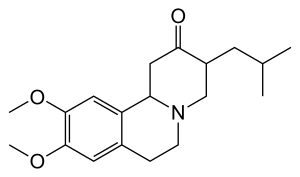

وهذا المرض ليس له علاج، وإن كان كثير من أعراضه يمكن تخفيفها عن طريق الأدوية والطرق العلاجية الأخرى.